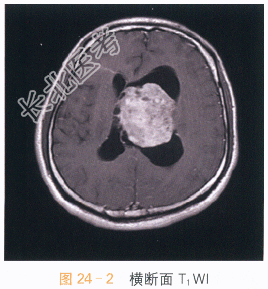

影像学资料如图24-1~图24-4所示。

读片分析:头颅MRI检查横断面T₂-Flair可见左侧侧脑室及透明隔区不规则软组织肿块,呈等高信号影,病灶内可见小片状囊变影,左侧侧脑室扩大,右侧侧脑室受压;增强扫描可见片状不均匀明显强化,囊变区无明显强化。结合患者病史,可考虑诊断为中央神经细胞瘤。